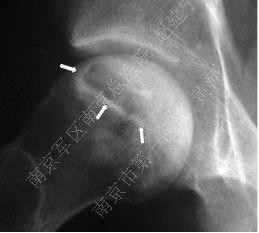

2.影像学检查: 髋部正位片及蛙式位片仍是重要的诊断手段,正位片最初的阳性表现为头下的硬化带及囊性改变,由于正位片中髋臼前后缘与股骨头上方存在重叠,有可能导致病损区显示不清,因此蛙式位片不可或缺,随着病情发展,软骨下骨与软骨分层,X片上则表现为新月征的特点;由于疾病早期X片可无阳性表现,MRI是目前诊断ONFH的“金标准”,其特征性体现在T1加权像上的低密度信号以及T2加权像的高密度信号,是坏死骨与活性骨的交界处出现大量富含血管的肉芽组织的表现。

囊性变及硬化带

新月征

病损周围环绕硬化带(白箭头)软骨下骨折(黑箭头)以及关节间隙狭窄(细长白箭头)

股骨头坏死进展性变化:病损周围硬化带

(白箭头),关节面塌陷,关节间隙严重狭窄,

髋臼软骨下囊肿形成(细箭头)